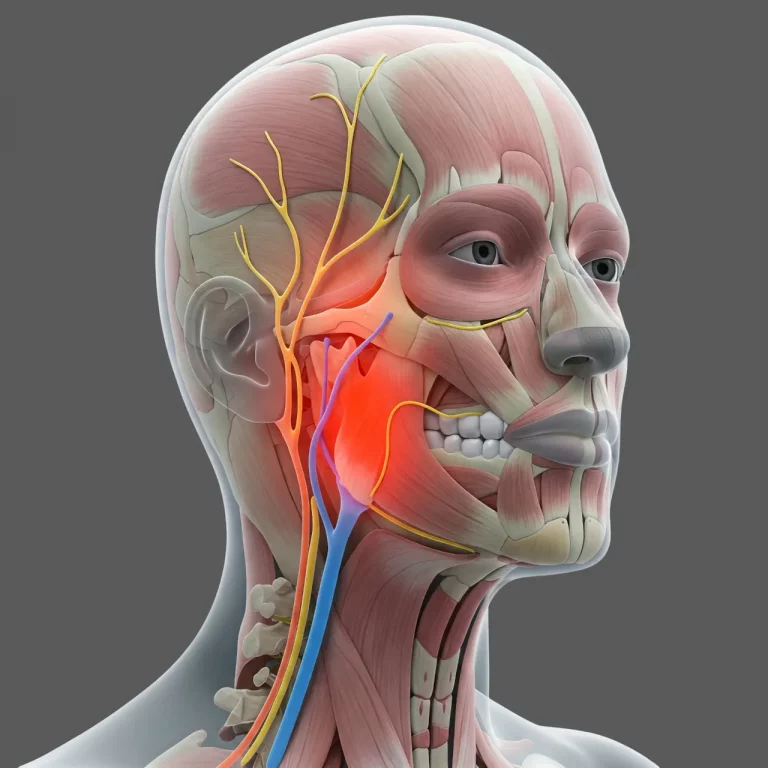

Гострий біль, що прострілює по нозі, ніби хтось тягне за невидиму нитку, або обличчя, яке кривиться в...